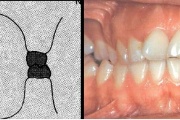

Normaalse jäävhammaskonna pilt küljelt ja eest vaadatuna.